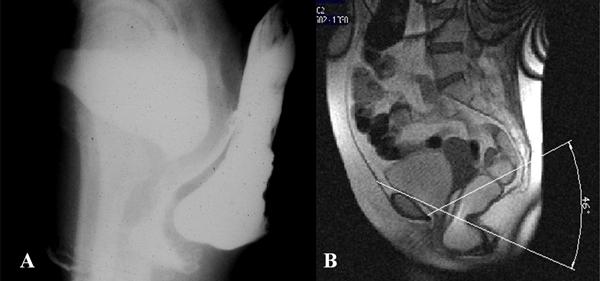

The prevalence of pelvic floor hernias at conventional radiology was higher if compared with that at MRI. Concerning the hernia content, there were significantly more enteroceles and sigmoidoceles on conventional radiology than on MRI, whereas, in relation to the hernia development modalities, the prevalence of elytroceles, edroceles, and Douglas' hernias at conventional radiology was significantly higher than that at MRI.

MRI shows lower sensitivity than conventional radiology in the detection of pelvic floor hernias development. The less-invasive MRI may have a role in a better evaluation of the entire pelvic anatomy and pelvic organ interaction especially in patients with multicompartmental defects, planned for surgery.

与MRI相比,传统放射学检查中盆底疝的患病率更高。关于疝内容物,传统放射学检查中肠膨出和乙状结肠膨出明显多于MRI检查;而关于疝的发展方式,传统放射学检查中阴道膨出、会阴疝和Douglas疝的患病率明显高于MRI检查。

在检测盆底疝的发展方面,MRI的敏感性低于传统放射学。侵入性较小的MRI在更好地评估整个盆腔解剖结构和盆腔器官相互作用方面可能具有作用,尤其是对于计划进行手术的多腔室缺陷患者。